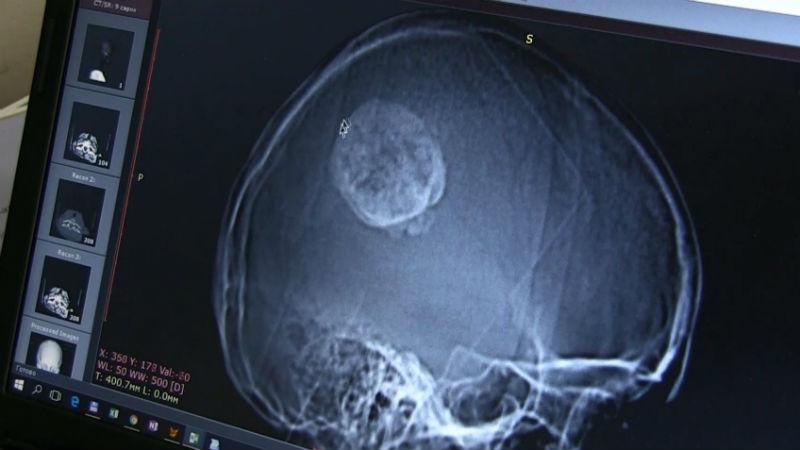

На знімку голови 32-річної пацієнтки перед втручанням видно велику пухлину і щось схоже на гачок, який вчепився в мозок. У цій частині до нього не підібратися.

Операція тривала майже чотири години. З рідкісною пухлиною боролися шестеро найкращих медиків. Та дістати закостенілу пухлину, не зачепивши мозок вдалося. Кошти на складну операцію зібрали люди, яких вразила історія жінки.